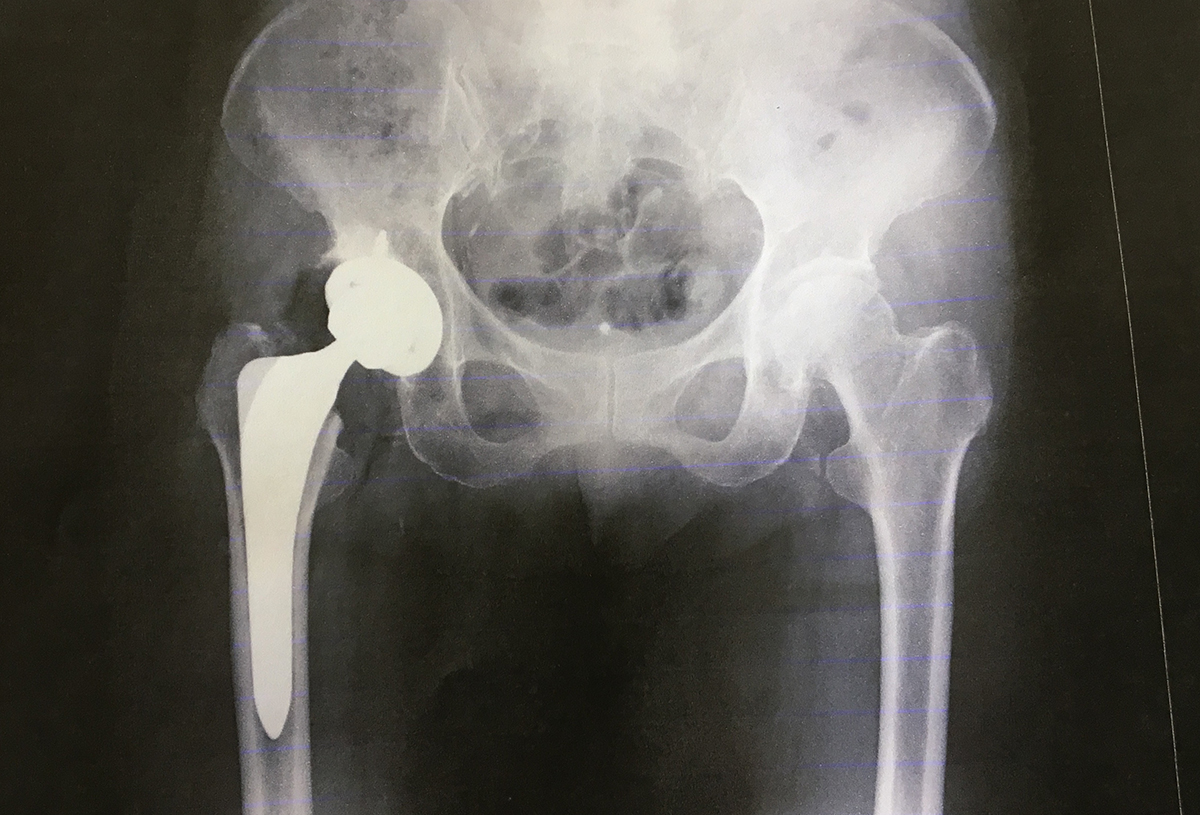

やはり、びっこが続き、痛みが増し、とある病院に再度診察へ行ってみると、先生が「今度は膝ではなく股関節をレントゲン撮ってみましょう」と撮ってみたところ、ペルテス病と診断されました。

※1どんな病気?   子どもの股関節の大腿骨の頭の部分への血行が何らかの原因で途絶され、骨の壊死(骨の細胞が死んでしまう)がおこり、骨の強度が極端に弱くなり、放置しておくとつぶれて骨に変形が生じてしまう病気です。

小学校1年生から6年生まで入園しました。退園する時、小さかったので鮮明には覚えていないのですが、先生が「つよし君の股関節は右と左、形が違うからね。少しつぶれて治ったからね」、そんなことをおっしゃっていたかと思います。

これは明らかにおかしいと最寄りの整形外科で診てもらったところ、変形性股関節症と診断されました。何か所かの病院を渡り歩き、令和5年11月20日に人工股関節置換術を受けることになりました。→ここからのエピソードは闘病日記を参照してください。